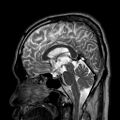

1. 3D T1 TFE CE(turbo field echo, contrast-enhanced)

1. 대표사진

2. 1mm 간격으로 촬영한 사진 160장으로